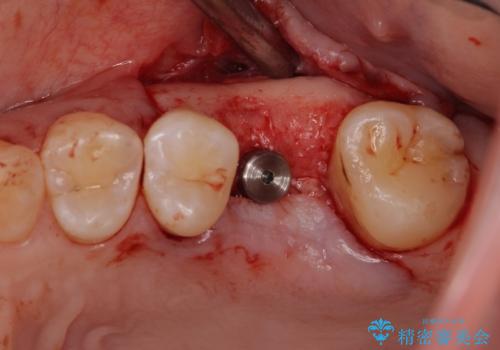

抜歯の上インプラントによる補綴治療を行うこととなりましたが、前歯の叢生も気になるとのことで並行して矯正治療を行うこととしました。

歯列不正は軽微であったので、インビザラインによる矯正治療とし、矯正治療中にインプラント埋入を行う予定としました。

痛みがないので、ボロボロのまま放置していましたが、抜歯後は汚れが溜まりにくくなりスッキリとしたようです。

- 外科手術のため、術後に痛みや腫れ、違和感を伴います